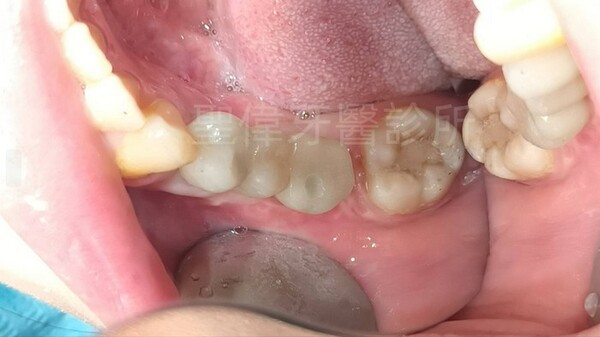

缺牙這件事一開始其實沒有被我放在心上 因為位置不在正中間,平常不太容易被看出來

但後來發現吃東西,很容易磨破我缺牙那邊的牙肉

![]() 實際進行植牙的過程,氛圍真的很輕鬆完全不會緊張

恢復期間生活沒有被打亂太多,只是吃東西會多注意一點